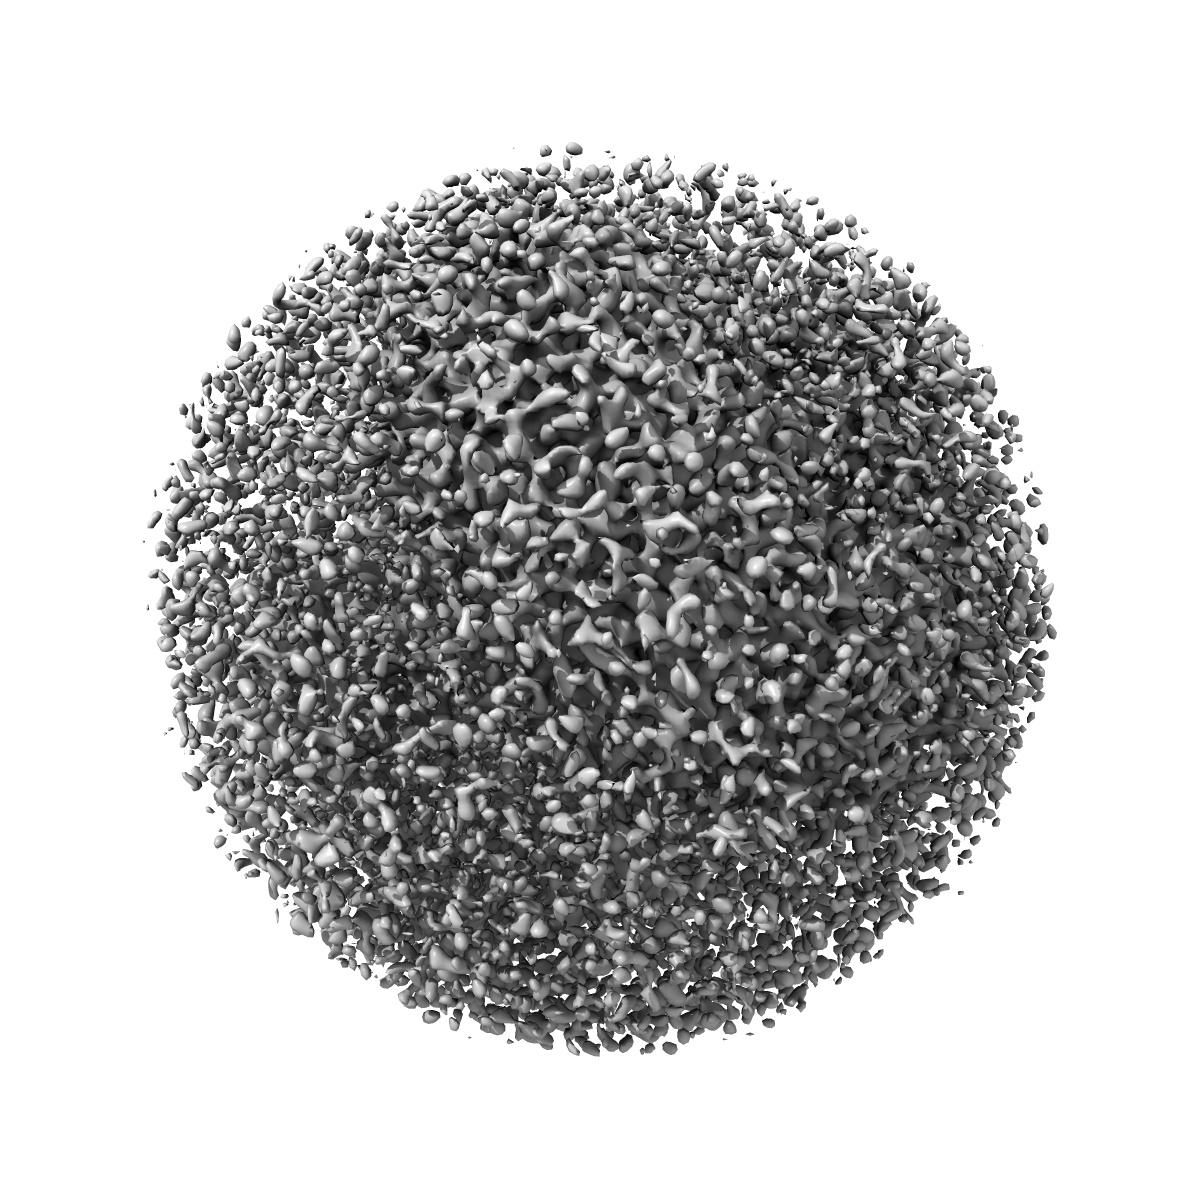

Structure of the cystic fibrosis transmembrane conductance regulator (CFTR) from zebrafish

Sample Organism: Danio rerio

Sample: Cystic fibrosis transmembrane conductance regulator or ABCC7

Fitted models: 5uar

Deposition Authors: Zhang Z, Chen J

Atomic structure of the cystic fibrosis transmembrane conductance regulator

Zhang Z, Chen J

(2016) Cell , 167 , 1586 - 1597

DOI: doi:10.1016/j.cell.2016.11.014